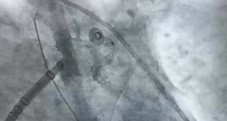

术前,介入手术室联合心血管内科、麻醉手术中心、超声医学科、重症医学科等多学科团队,依托Carto三维电解剖标测系统及心腔内超声(ICE)技术,全面重建患者心脏结构,精准定位肺静脉及左心耳。

团队率先为患者实施全麻下房颤射频消融术,随后,经ICE实时引导,将Watchman FLX封堵器精准释放在左心耳开口处,术后造影及超声验证封堵完全无残余分流。